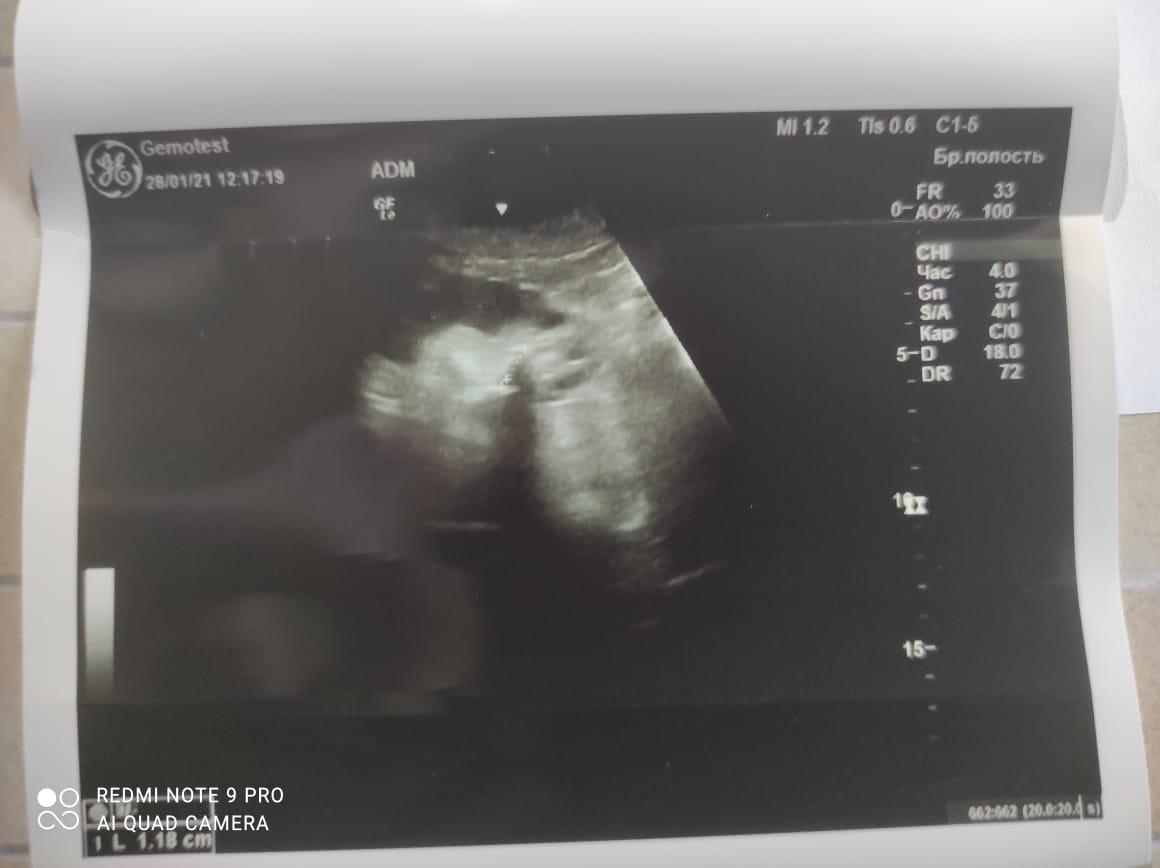

Здравствуйте! При наличии коралловидного камня правой почки(заключение УЗИ), можно предположить причиной боли нарушение уродинамики верхних мочевых путей), что, однако, не подтверждается результатами УЗИ почек( ЧЛС не расширена). Другая, наиболее вероятная возможная причина "боли в боку" - может быть патология опорнодвигательного аппарата. Необходимо проконсультироваться с неврологом и урологом очно, и согласовать возможность применения противовоспалительных, обезболивающих и спазмолитических препаратов - как первый шаг. В дальнейшем необходимо планировать возможное дальнейшее обследование и лечение. Удачи!